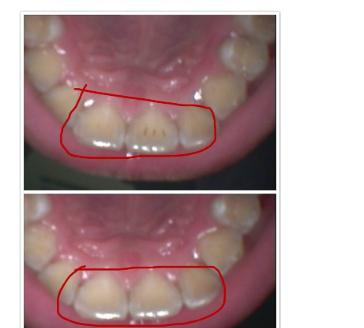

1、洗牙原因:一般情况下洁牙后都会配合“抛光”操作,如果没有抛光,或者说抛光不彻底(和每颗牙抛的时间,所用的抛光杯和粉,有没有抛2“3个牙面)都有关系。

2、个人原因:洁牙后在24-48小时内就开始吸烟、饮用有色素的东西。

3、其他原因:牙釉质本身发育不好,因此有时候就是抛光完之后也容易在段时间内染色。